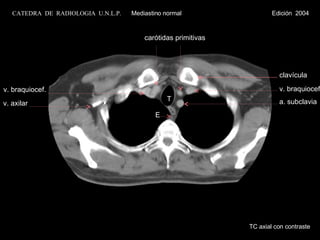

TC axial con contraste v. braquiocef. T E carótidas primitivas a. subclavia v. braquiocef. v. axilar clavícula CATEDRA  DE  RADIOLOGIA  U.N.L.P.   Mediastino normal  Edición  2004

TC axial concontraste v. braquiocef. T E carótidas primitivas a. subclavia v. braquiocef. v. axilar clavícula CATEDRA DE RADIOLOGIA U.N.L.P. Mediastino normal Edición 2004